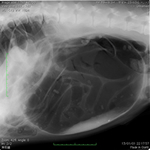

症例1

プロフィール:バーニーズマウンテンドッグ、9歳、雄

主訴:急にお腹が張ってきて、吐きそうで吐けない。

身体検査所見:腹囲膨満、鼓音を認める。

X線検査所見:胃拡張、180°捻転を認める。

評価:胃拡張捻転。手術による治療を実施。術後の経過は良好であった。